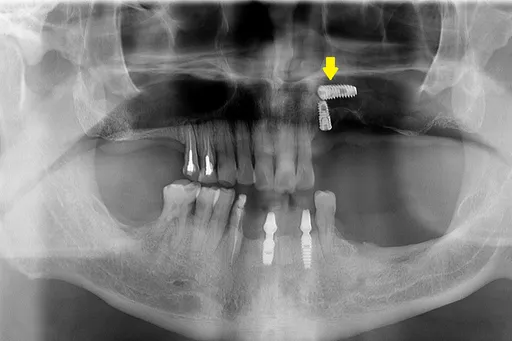

植牙后高烧脸肿 竟是人工牙根掉入鼻窦!2原因害他险失明

...二至三成的人有多颗缺牙,除了做全口假牙或活动假牙,人工植牙也是常见治疗方式。但如果在植牙手术前未充分...